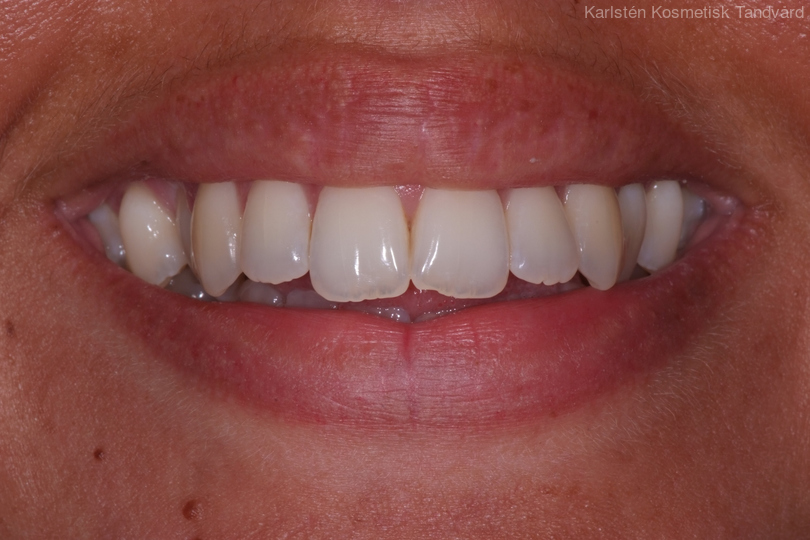

Tandreglering 1

Ung kvinna som tidigare haft tandreglering. Upplever inte att tänderna står i en fin tandbåge. 11 månaders behandling med genomskinliga Invisalignskenor resulterade i ett fint leende.